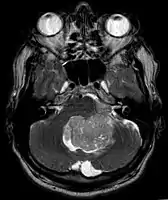

Ependymoma of 4.ventricle in MRI.